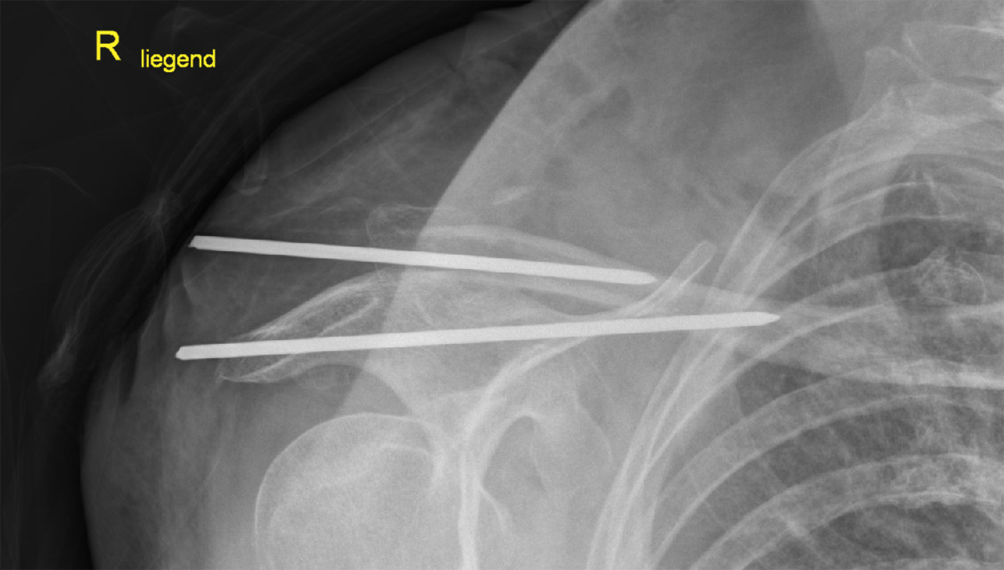

Bei einer Röntgenkontrolle zur Planung der Materialentfernung bei sonst asymptomatischer Patientin zeigte sich eine Verlagerung des verbliebenen K‑Drahtes nach intrathorakal/mediastinal (Abb. 2). Eine auswärts durchgeführte native Computertomographie (CT) bestätigte die Dislokation des K‑Drahtes und zeigte eine Perforation beider Pleurahöhlen und die Migration in das Mediastinum. Der K‑Draht verlief dorsal der A. vertebralis, zwischen Trachea und Ösophagus ohne eine Läsion dieser Strukturen (Abb. 3).

Abb. 3

a Transversale CT-Schnittebene mit Darstellung des migrierten K-Drahtes zwischen Trachea und Oesophagus. b Sagitale CT-Schnittebene mit Darstellung des migrierten K-Drahtes zwischen Trachea und Oesophagus